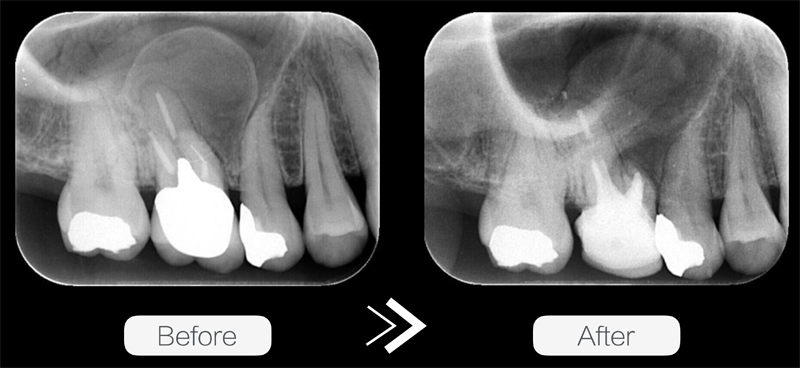

右上奥歯がたたくと痛い、浮いた感じがするという主訴で来院されました。

レントゲンを撮り、歯の根にできた膿の袋

を確認しました。

黄色い点線部分が膿の袋です。

このままでは隣の歯も感染してしまいます。

かなり歯根膿胞は大きく、レントゲンだけでは3次元的にどのようになっているのかが診断できないので、CTを撮影し精密な検査をおこないました